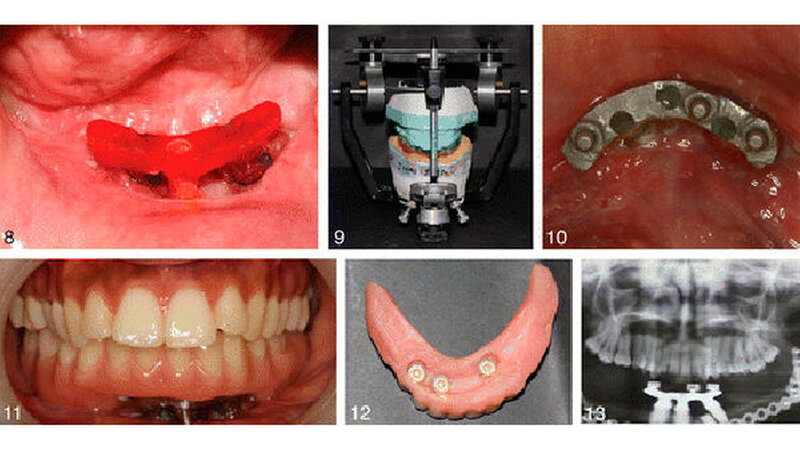

Der Fall:In diesem Fallbericht geht es um eine 24-jährige Frau. Eine Geschwulst in ihrem Kiefer war drei Jahre zuvor entfernt und der Kiefer mit Material aus einem ihrer Wadenbeinknochen wiederaufgebaut worden - ohne Erfolg. In einer zweiten OP wurde der Eingriff wiederholt. Zusätzlich wurden vier Implantate inseriert und eine Zahnprothese eingefügt.

Nach zwei Jahren berichtet die Patientin, dass sie mit der Prothese sehr gut zurecht kommt und abgesehen von Nüssen und Fleisch ganz normal essen kann. Sie spricht klar und deutlich, und ihre Gesichtsproportionen sind im Vergleich zu vorher symmetrischer.

Einmal mussten die Plastikbefestigungen aufgrund von Abnutzungserscheinungen ersetzt werden. Die Patientin ist ansonsten gesund und geht ihren täglichen Tätigkeiten nach. Sie fühlt sich wohl mit in ihrem Äußeren und hat keine Probleme mit dem Bein, das als Spenderseite verwendet worden war.